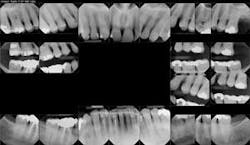

Figures 2a and 2b: Initial presentation in 2011 of the upper right and left molar area, showing advanced bone loss with furcation involvement on the molars.

At presentation, Martin was in his fifties with a medical history significant for controlled hypertension with no known food or drug allergies. He had been lackadaisical with his dental care in the past because of his busy schedule, but he was motivated to get his hygiene and treatment under control. He denied a history of smoking/alcohol/drug use. Based on his full-mouth series (figure 1) and clinical presentation, Martin had generalized, moderate bone loss with localized, severe bone loss in the posterior maxillary right and left quadrants (figures 2a and 2b) as well as the mandibular anterior incisor area (figure 3).